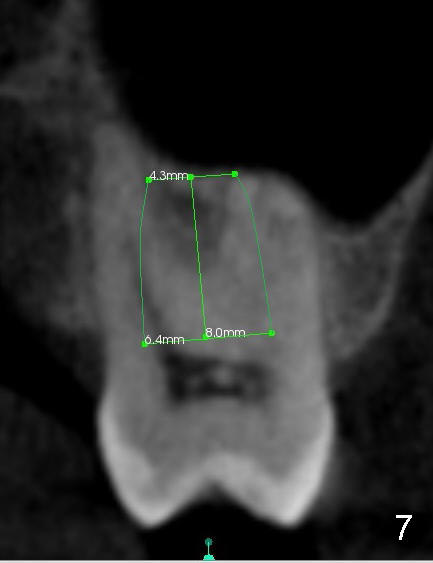

When the buccal roots are fused, there are 3 potential sites for immediate implant (Fig.1'): septum (*), buccal (B) and palatal (P) sockets. Septal placement (6.9x8 mm bone level implant) is the most ideal for restoration (Fig.3). The length of the implant can be increased (10 mm) with sinus lift so that the base of the implant between the buccal and palatal apices in height (Fig.4). Primary stability is derived mainly from the implant body engagement into the septum (Fig.5 coronal section through the septum). If bone density in the septum is high, a small implant may be appropriate (Fig.6,7: 6.4x8 mm). The large implant (6.9 mm) is chosen so that amount of bone graft to be used (Fig.8 red circles) is less.